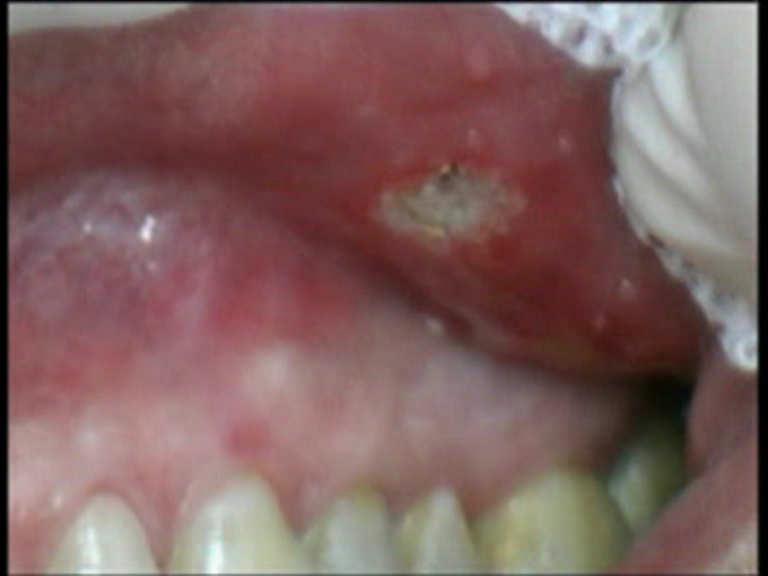

Laser Setting – Diode Laser 810nm

Power: 2.0 Watt, CW

Fibre 400 micron

Spiral-shaped movement around the aphtha

20 seconds with air refrigeration